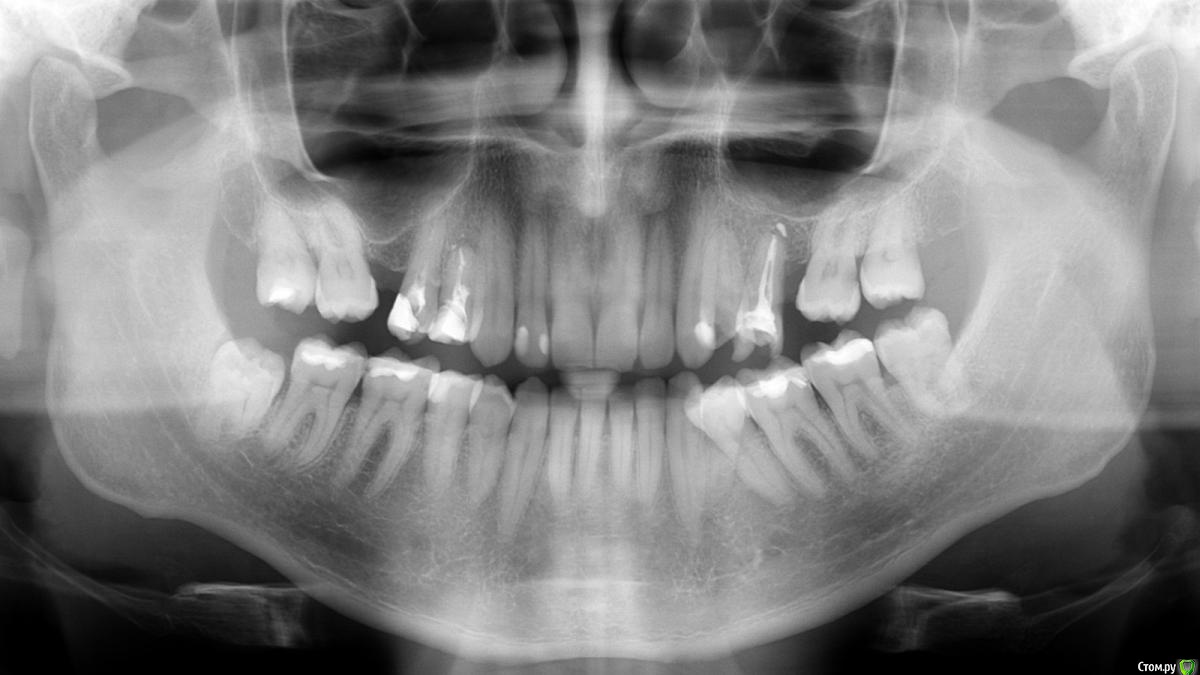

red_butler Опубликовано 17 ноября, 2015 Поделиться Опубликовано 17 ноября, 2015 Начните с панорамного снимка и покажите его нам. 2 Ссылка на комментарий

Александр9 Опубликовано 18 ноября, 2015 Автор Поделиться Опубликовано 18 ноября, 2015 Спасибо за ответы. Собираюсь получить снимок и выложить ортопантомограмму сегодня ( в четверг) вечером.Предварительно мне предложили поставить четыре металлокерамические коронки, помимо нескольких пломб и лечения клиновидных дефектов на нескольких зубах.Пока собираюсь во время посещения для снимка ортопантомограммы сделать сразу же чистку от зубов камня (airflow) до начала остального лечения. Имеет ли смысл или чистку лучше делать ближе к концу? Ссылка на комментарий

Александр9 Опубликовано 20 ноября, 2015 Автор Поделиться Опубликовано 20 ноября, 2015 (изменено) У меня разрушен 24 зуб и очень плох 25. На другой стороне 14,15 также не совсем хороши (16 отсутствует как и 26).Мне предлагается поставить коронки на эти четыре зуба. Но перед этим по-видимому надо подлечить остальные зубы: обновить несколько пломб и почистить каналы.Хотелось бы растянуть (из финансовых соображений) сроки лечения. Т.к. хочется поскорее сделать "красивым" 24 зуб (виден если широко улыбаться), то посоветуйте пожалуйста что целесообразно сделать в первую очередь? Изменено 20 ноября, 2015 пользователем Александр9 Ссылка на комментарий

DmitrySH Опубликовано 20 ноября, 2015 Поделиться Опубликовано 20 ноября, 2015 Начните с лечения каналов 24, 25, 14, 15.Впринципе 25 нормально запломбирован по снимку, но надо оценить геметичность пломбы и понять чем запломбировано.Кариес на 27, 46. Остальные пломбы визуально смотреть. Далее, у Вас из-за длительного отсутвия 16, 26 - произошло смещение зубов. Соответвенно нужна консультация ортодонта.Если заниматься ортодонтическим лечением, то верхние 15,14,24,25 на время ортодонтии восстановить пломбами или временными коронками ( по ситуации) после ортодонтии изготовление постоянных коронок Ссылка на комментарий